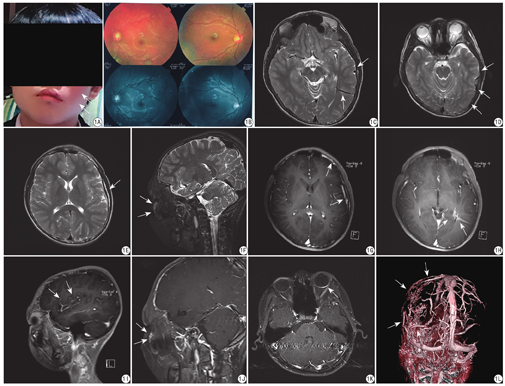

患者男,12岁。A:左侧面颊部红斑痣;B:眼底照相检查左侧眼部血管增多、迂曲;C:轴位T2WI平扫左侧颞叶脑表增粗、迂曲流空血管及左侧颞、枕交界区脑实质内发育异常流空血管;D:轴位T2WI平扫左侧颞叶脑表迂曲流空血管影;E:轴位T2WI平扫示左侧颞骨内板增厚;F:矢状位T2-tirm平扫示左侧面颊部皮下高信号迂曲血管;G:轴位T1WI增强扫描左侧额、颞叶脑表强化血管影;H:轴位T1WI增强扫描示左侧颞、枕交界区脑实质内强化引流血管影,向内延伸与左侧侧脑室后角脉络丛相通;I:矢状位T1WI增强扫描示颞叶脑表增多强化血管;J:矢状位T1WI增强扫描左侧面颊部皮下迂曲强化血管影;K:轴位T1WI增强扫描左侧眼球后壁增厚并强化;L:三维容积重建图示左侧颞、顶叶脑表迂曲增多血管,左侧颞、枕交界区一发育异常血管

A 12-year-old male patient. A: Red mole on the left cheek; B: Fundus examination showed increased blood vessels and tortuosity in the left eye; C: Axis T2WI plain scan of left temporal lobe cerebral surface thickening, tortuosity and empygoid vascular shadows, and abnormal development of empygoid vascular shadows in the left temporal and occipital junction area; D: T2WI plain scan of tortuous, empty vascular shadows on the left temporal lobe surface; E: T2WI plain scan of the left inner temporal bone plate thickened with high signal; F: Sagittal T2-tirm plain scan showed hypersignal tortuous vascular shadows in the left cheek; G: Axis T1WI enhanced angiography on the left frontal and temporal lobes of the brain; H: Axis T1WI enhanced scan showed enhanced drainage vascular shadows within the brain parenchyma in the left temporal and occipital junction, extending inwards and connecting with the choroid plexus of the posterior horn of the left lateral ventricle; I: Sagittal T1WI enhanced scan showed increased temporal lobe cerebral surface and enhanced vascular shadow; J: Sagittal T1WI enhanced scan on left cheek with subcutaneous tortuous enhancement of vascular shadow; K: T1WI enhanced scan on the left posterior wall of the eyeball thickened and strengthened; L: 3D volume reconstruction shows increased tortuous vessels on the left temporal and parietal lobes, and abnormal vascular shadows in the left temporal and occipital junction.

MRI检查:轴位T2WI示左侧颞、枕叶脑表迂曲、增多流空血管;左侧颞、枕交界区脑实质内见一粗大发育异常流空血管向左侧侧脑室后角延伸;左侧颞骨内板局限性增厚。矢状位T2-tirm可见左侧面颊部皮下血管增多、迂曲。轴位T1WI增强扫描见左侧额、颞叶脑表迂曲、增多的血管内有对比剂充填;左侧颞、枕交界区脑实质内强化的粗大发育异常引流血管向深部延伸与左侧侧脑室后角脉络丛相沟通,左侧眼球后壁增厚、强化。矢状位T1WI增强扫描见左侧面颊部血管增多、迂曲。三维容积扫描重建图示左侧颞叶、顶叶脑表血管迂曲、增多,左侧颞、枕交界区见粗大发育异常的引流血管,见图1C~1L。